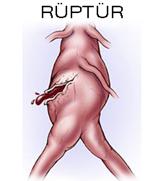

Ancak son birkaç gündür devam eden ve özellikle hipertansiyonla beraber olan karın, sırt ve bel ağrıları anevrizmayı düşündürmelidir. Bunun yanında anevrizmanın patlaması anlamına gelen rüptürde şikayetler tamamen farklıdır.

Ancak son birkaç gündür devam eden ve özellikle hipertansiyonla beraber olan karın, sırt ve bel ağrıları anevrizmayı düşündürmelidir. Bunun yanında anevrizmanın patlaması anlamına gelen rüptürde şikayetler tamamen farklıdır.

Rüptür ani bir iç kanamaya yol açarak sıklıkla ölüme neden olur. Daha önce anevrizması olduğu bilinen yada bilinmeyen bir kişi ani gelişen şiddetli bel ve karın ağrısı ile beraber bayılma, tansiyon yüksekliği yada düşüklüğü durumunda rüptür akla gelmeli ve hemen hastaneye başvurulmalıdır.